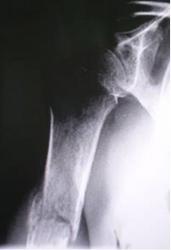

Протокол. На обзорной цифровой флюорограмме правого плечевого сустава (1), произведенной в прямой стандартной проекции, со стороны плечевого сустава изменения возрастного характера. В месте перехода проксимальной трети диафиза в среднюю, на фоне выраженной патологической перестройки структуры костной ткани, определяется линия поперечного «патологического перелома», с некоторым смещением отломков по ширине. Произведена дополнительная цифровая обработка изображения в условиях увеличения изображения и эквилизации (2, 3) для лучшей детализации области перелома.

1. обзорная цифровая флюорограмма правого плечевого сустава